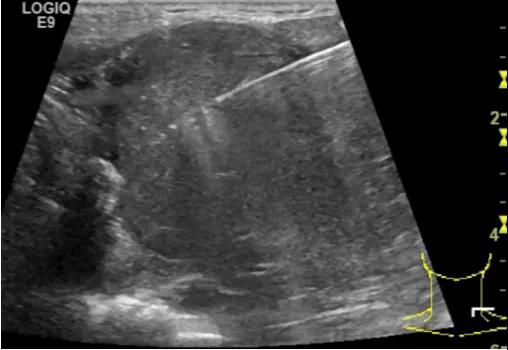

第二例是食管癌患者,术后半年余锁骨上固定淋巴结可触及肿大,疼痛非常明显,系统治疗后无缓解,患者希望通过局部处理缓解症状。造影显示强化信号明显,结节部分区域坏死,故主要针对强化区域从后向前的逐层的消融,皮下进行液体隔离减少烫伤。热消融后影像显示血流增强消失,弹性、硬度增高,一个月后复查显示充盈缺损,完全消融,疗效远超预期。

(病例2图例)